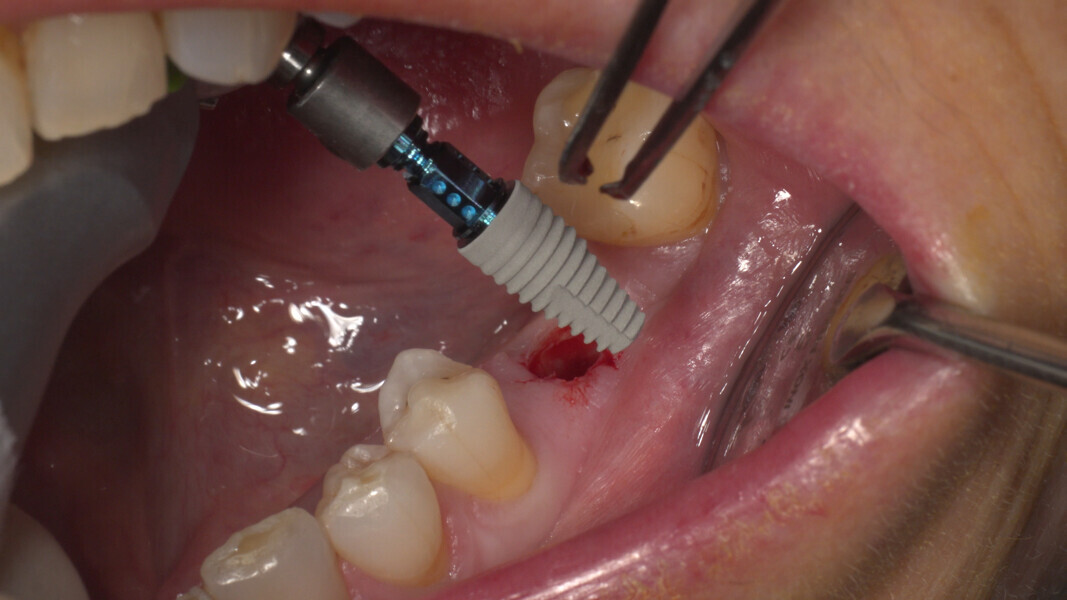

Conventional and immediate loading with final n!ce screw-retained crowns